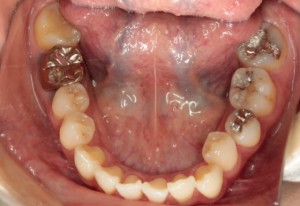

CRによるダイレクトボンディング法

左下奥歯の3本をCRにより修復しています。(保険and自由診療)

作成前